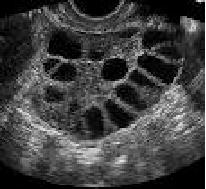

超声监测排卵

我们一般通过观察卵泡来推测卵子的发育情况掌握受孕的时间。卵泡发育最简单、最直观的评估是通过超声观察,每个周期通过3~4次的超声监测。①最大的卵泡直径<1cm时,监测时间间隔为6-7天左右;②优势卵泡直径1.0-1.2cm,监测的时间间隔为3-4天左右;③优势卵泡直径1.3-1.5cm,监测的时间间隔为2-3天左右;④优势卵泡直径≥1.6cm时,监测时间间隔为1-2天左右。卵泡发育判断标准:①卵泡正常发育:卵泡直径 ≥18-20mm,排卵期动脉收缩期峰值流速/舒张末期血流 速度(S/D)值为(2.66±0.24),卵泡性状饱满、张力大,卵泡壁薄,卵泡壁分布内有环状血流,卵巢血流灌注丰富;②卵泡异常发育:患者排卵期RI>0.8,卵泡直径<15mm,无周期性变薄,卵巢内血流灌注较差,卵泡壁分布处有条状血流[2]。

如果患者月经不规律、月经稀发,超声提示卵巢内窦卵泡数较多,一侧或两侧卵巢内各有12个及以上直径为2-9mm无回声区,围绕卵巢边缘,呈“车轮状”排列,称“项链征”,考虑“多囊卵巢”,常规的观察排卵未见优势卵泡发育,需要医生根据内分泌、AMH、超声检查以及临床表现等结果给予药物治疗,以帮助卵泡生长。